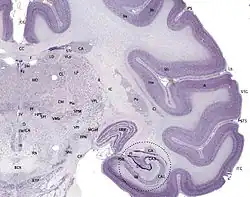

Cresyl violet stain

Cresyl violet is used to stain Heinz bodies in red blood corpuscles or for staining of the neurons in the brain and spinal cord. It is used to demonstrate the Nissl substance in the neurons and cell nuclei. In this role it is also often used as a counterstain to Luxol fast blue, which stains the myelin.